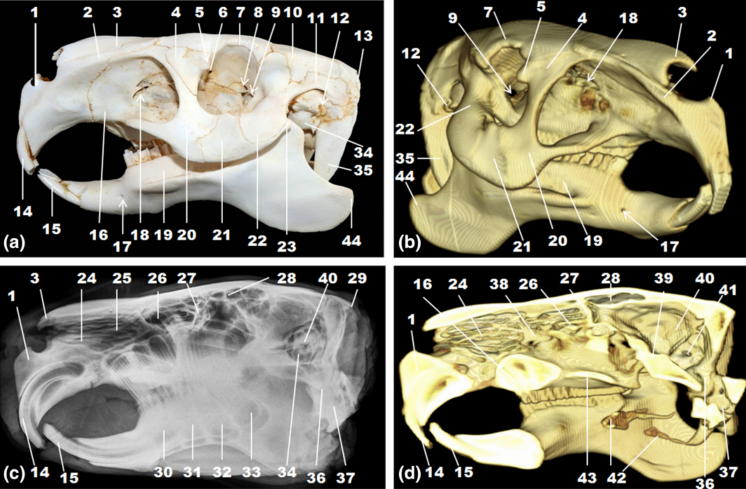

カピバラの頭蓋骨形状に関しては以下の論文が最近発表されましたので苦言も交えつつご紹介しましょう。とは言うものの、無料で手に入るのは抄録と付図のみになります。 『レントゲン並びに3D CTを用いたカピバラ頭蓋骨の解剖』https://onlinelibrary.wiley.com/doi/abs/10.1111/ahe.12531Anatomy of the skull in the capybara (Hydrochoerus hydrochaeris) using radiography and 3D computed tomographyF. Pereira, et al., First published: 25 January 2020Anatomia Histologia Embryologia, Volume49, Issue3, May2020, Pages 317-324https://doi.org/10.1111/ahe.12531AbstractThe capybaras (Hydrochoerus hydrochaeris) are the largest rodent found throughout South America and are present in almost all the Brazilian territory, however, still lack basic descriptions about the species, such as about their cranial anatomy. This study was carried out to investigate the anatomical features in the capybara skull. Eight skulls and two heads, without sexual distinction, were used for the osteological, radiographic and tomographic identification of their structures. The skull of the capybara could be divided into a neurocranium and aviscerocranium. The capybara had a more robust and rectangular skull, elongated face caudally, thinned in the nasal region and slightly convex inthe parietal region. The zygomatic arch was expanded and wide, the orbit had a circular shape, the infraorbital foramen was well developed,external acoustic meatus and tympanic bulla were relatively small, and the paracondylar process was large. These anatomical characteristicsare compatible with the eating habit and semi‐aquatic life of capybaras, which can be compared with characteristics reported for animals ofsimilar habits. The radiographic image allowed to identify structures such as the frontal sinus, whereas 3D tomographic reconstruction wasessential to have a spatial view of the skull of the capybara.抄録カピバラは南米大陸を通じて観察される最大の齧歯類であり、ブラジルのほぼ全土に棲息する。しかしながら、本種については例えば頭蓋形態と言った、基礎的な記述が依然として欠けている。本研究はカピバラ頭蓋骨の解剖学的特徴を調べるべく遂行された。性別判定を欠く8個の頭蓋骨並びに頭部を用い、レントゲン画像と断層画像からそれらの骨学的な構造同定が行われた。カピバラの頭蓋骨は神経頭蓋と内臓頭蓋に区別し得た。カピバラ頭蓋骨はより頑丈で長方形を呈し、顔面部は尾方に伸張し鼻領域は骨質が薄く、頭頂部は軽度に凸状を示した。頬骨弓は拡張して幅が広い。眼窩は円形で眼窩下孔は良好に発達し、外耳孔及び鼓室胞は相対的に小さいが、顆傍突起は大きかった。これらの解剖学的特徴は、カピバラの食性並びに半水棲に対応しているが、同様の習性を持つ動物に報告されている特徴に比較検討され得る。レントゲン像に拠り例えば前頭洞と言った構造を同定することは可能だが、一方、3D 断層像を元にしての復元像はカピバラ頭蓋骨の立体像を得るのに必須である。(院長訳) |

若手の院生などが執筆したペーパーかと思いますが、要は、CTスキャンしてみました、との業務報告の域を出ないものと感じます。院長はこの論文のタイトルと抄録含め全面的に書き直したい衝動に駆られてしまいました。付図も正しい側方 aspect の図が無かったり、コントラストの悪いX線像を載せたりと形態学に対する緊張感に不足するものと率直に感じました。 抄録を目通ししただけの感想に過ぎませんが、特に形態学面で重要な発見や新奇な考察を行い得たものではなく、観察された特徴がカピバラの食性並びに半水棲に関与している可能性があるとの凡庸な、浅い考察に留まります。院長が指導教官であれば、「君、せめて同じ南米大陸に棲息する齧歯類の、カピバラの近縁種のコモ、半水棲のヌートリア、地上性のマーラ、ついでに?モルモットで比較を行うなどして、系統並びに運動性、食性等含めもう少し深い物言いは出来ないかね?」となりそうです。可能ならば顔つきや形態的特徴の類似するモンゴル平原に棲息する掘削性の大型齧歯類マーモットとの比較も行うと面白いでしょうね。特に、冒頭の、「基礎的データが無いので記載してみました」云々の文言を一目見て、もう少し工夫して洒落た表現に出来なかったのかと思わされます。一度に長い論文を執筆する風潮にはありませんので、この様な計画を建てて小出しに論文化、投稿して行く訳です。 解剖学はメスとピンセットがあれば出来るなどと宣う者も見受けられますが、それは利用する道具に過ぎず、全ての学問分野と同様、高度な頭脳が無ければ深い考察には繋がりません。これを勘違いして、第三者が検証しにくい珍奇な動物種を用い、面白い動物を<メスとピンセットで>解剖しましたと、誰もが考えつく程度の月並みで浅い考察もどきを行い、ペーパーをさっと仕上げる者が出現したりもします。院長も過去にその手の投稿論文の審査を担当し辟易したことがあります。論文にとって最重要なキモである考察の分量が極く少なく、どの様な視点から解剖を執り行ったのかの根源的な説得性−これこそが形態学の学問としての神髄−を持たないのです。メスとピンセットで剖出すること、或いはCTスキャンで画像を撮影したところで、それは単なる dissection 切り刻みの類いに過ぎず、morphology 形態<学>ではありません。この様な勘違いな遣り方を続けていると、素人さんやマスコミには受けるかも知れませんが、仲間内では、<こいつ、形態学の土俵に乗り、敵方とがっぷり組んで討論しようとせず、いつも土俵外であれこれ次から次へと切り刻んでいやがる>と軽蔑を買うことに繋がります。 まぁ、いつまで切手収集のような調べ物を右から左に続けるのではなく、考えを深めることが大切です。。 ヒトの医学部などでも一頃解剖学教室など潰してしまえとの嵐が吹き荒れた様に朧に記憶していますが、学問・哲学ではなく、dissection を行うに留まる craftsman 集団と医学部内部で低く評定されたからかもしれません。仲間内から弁護すれば、解剖実習の負担だけでももの凄く、少しは勘弁して遣ってくれとは言いたくはなるのですが。 |